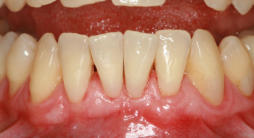

Bei der Parodontitis (Entzündung des Zahnbettes oder des Zahnhalteapparates) handelt es sich um eine chronische Erkrankung, die zum Abbau der zahntragenden Gewebe führt und mit Zahnfleischtaschen, erhöhter Lockerung des Zahnes, evtl. Schmerzen, bis zum Zahnausfall einhergeht. Parodontitis kann einzelne oder alle Zähne befallen und in seltenen Fällen schon bei Kindern und Jugendlichen auftreten. Sie verläuft lange still und unbemerkt und wirkt sich auch schädigend auf das Herz-Kreislaufsystem, Körperfunktionen und Organe aus.

Ursache für die Parodontitis sind bakterielle Zahnbeläge (Plaque) am Zahnfleischrand, die über lange Zeiträume bestehen und durch unzureichende Mundpflege entstehen. Die Bakterien der Plaque führen zunächst zur Entzündung des Zahnfleischsaumes (Gingivitis). Nach längerer Zeit vertieft sich die sog. Zahnfleischfurche zu einer sog. Zahnfleischtasche. In der Zahnfleischtasche können mehr und mehr Bakterien Platz finden. Schließlich greift die Entzündung auch auf die Knochenstrukturen des Zahnhalteapparates über. Damit ist eine Parodontitis entstanden, in deren Verlauf der zahntragende Knochen zerstört wird. Zusätzliche Faktoren, die das Entstehen einer Parodontitis fördern und den Verlauf verschlimmern, sind Rauchen, genetische Faktoren und bestimmte Erkrankungen des Gesamtorganismus (insbesondere Diabetes), funktionelle Überlastungen einzelner Zähne, unbehandelte Karies, Zahnengstände sowie überstehende Kronen- oder Füllungsränder, die Schlupfwinkel und damit Brutstätten für Bakterien bilden.